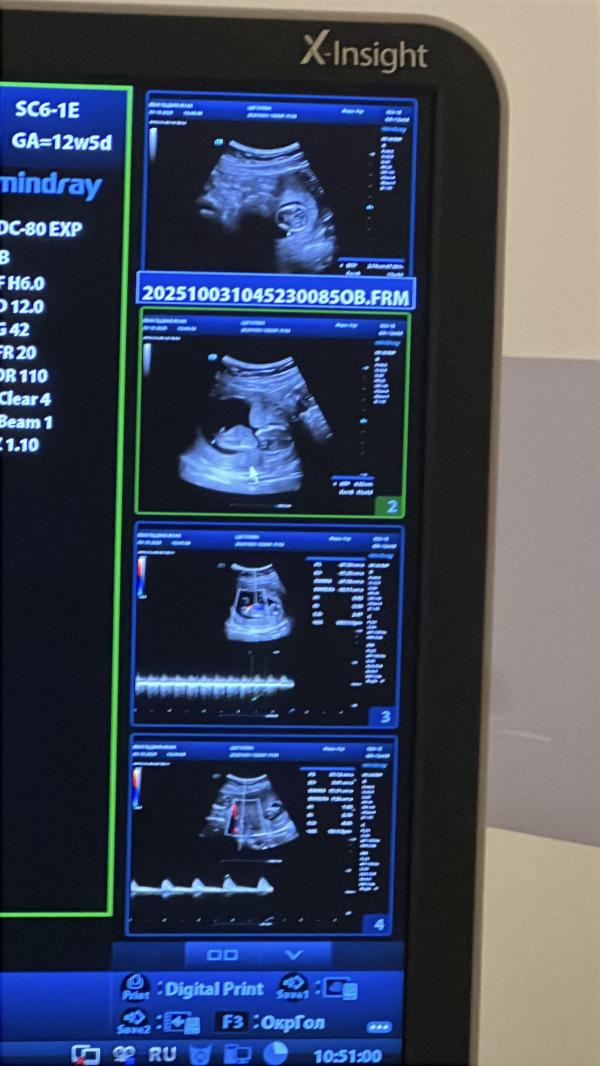

Проснулась и думаю «интересно, как сегодня пройдет первый скрининг?»🤣

Прошло всё отлично, с малышом все ок, сдала кровь и побежала обедать в кафетерий пц, люблю его всеми фибрами!